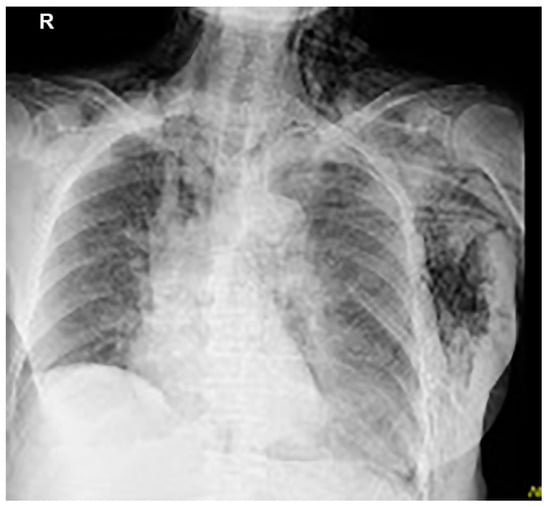

Thoracentesis and abdominocentesis were performed for detailed examination, and 1000 mL of each specimen was obtained. The cell block results of the obtained specimens indicated a suspected metastasis of high-grade serous carcinoma arising from the ovary. A biopsy under general anesthesia was scheduled to confirm ovarian cancer and to select drug therapy. However, after draining 1000 mL of pleural fluid, a large amount of left pleural fluid was still reaccumulated at the second examination two weeks later. Therefore, intubation under general anesthesia was judged to be high-risk. Therefore, the anesthesiologist requested the insertion of a left thoracic drain the day before. After the insertion of a thoracic drain, the patient was found to be COVID-19-positive on preoperative screening, and as a result, the patient’s biopsy surgery was postponed and the left thoracic drain was planned to be removed. However, considering that removing the drain immediately following insertion would be detrimental to the patient, removal was scheduled for the next day, to be followed by observation of the patient for several additional days. As planned, the drain was removed the day after insertion. However, approximately one hour following the drain’s removal, mediastinal and subcutaneous emphysema suddenly developed, with the patient also complaining of mild dyspnea. A left pneumothorax was then diagnosed using chest radiography. In addition, chest radiographic findings included mediastinal and subcutaneous emphysema observed in the anterior mediastinum and on the left side of the chest. Subsequently, a drain (20 Fr) was placed in the patient’s left thoracic cavity immediately after confirming the X-ray (Figure 2).

Figure 2.

Mediastinal and subcutaneous emphysema was observed in the anterior mediastinum and on the left sides of the chest, respectively.